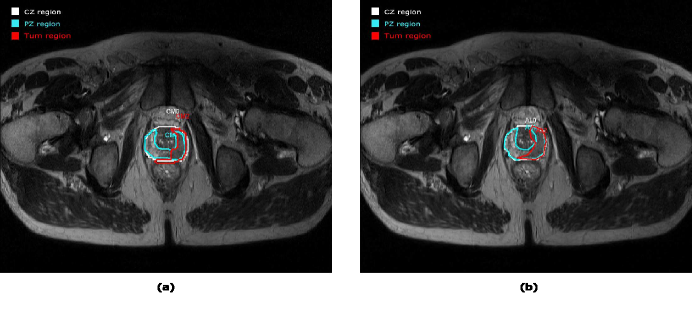

Refer to caption

Figure 1: Example of a PCa processing from E1 (left image) and from E2 (right image). Notice that the contours are similar for E1𝐸1E1 and E2𝐸2E2.

The purpose of the present study is to evaluate the variability between experts concerning medical findings in prostate gland regions. The differences observed for the delimitation of the different ROIs between independent evaluation or using a collaborative work by different users is studied. The idea behind this study is to show that collaborative work allows a real consensus between experts and potentially decreases variabilities in their evaluation. Figure 1(a) presents an example of the prostate gland analysis with manual drawing of the TZ (in white), PZ (in blue) and tumour area (in red). We have asked two experts to make these drawings independently on several MR examinations, and as a second step, one expert repeated the drawings with the knowledge of the evaluation of the other expert. Differences in the drawings such as in the volume calculations were compared in order to verify that there is a significant increase of the consensus in the results with collaborative work.

Two examples of a PCa analysis are presented in Figures 1 and 2. The left image in Figure 1 corresponds to the drawing by the first expert (E1)𝐸1(E1) and in the right image by the second expert (E2)𝐸2(E2). Three ROIs are drawn in both images corresponding to CZ (white), PZ (blue) and Tumour (red). When visually comparing the two drawings, a very good concordance between CZ and PZ areas can be observed. Concerning the tumourous area, a small deviation is found but contours could be considered as relativity close between the two experiments.